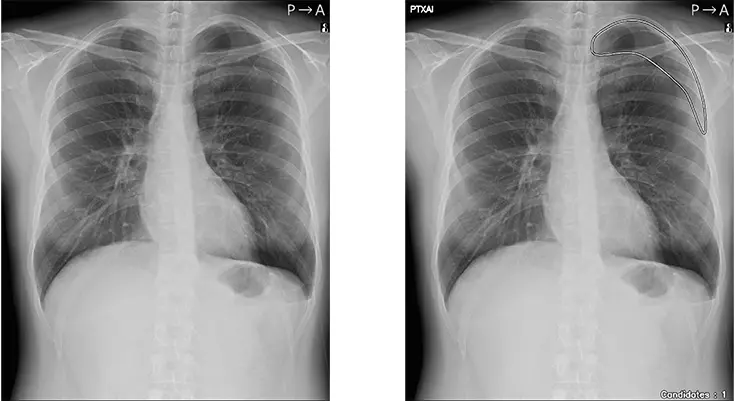

人のレントゲン写真 オリジナル画像

オリジナル画像

人のレントゲン写真 気胸の検出領域を表示

気胸の検出領域を表示

気胸とは、何らかの原因で肺に穴が開き、肺がしぼんでしまう状態を指します。胸の痛み、咳、息切れや呼吸困難などの症状を伴うことがあり、緊張性気胸に進展した場合には生命に危険が及ぶ可能性があります。そのため、早期発見・診断が重要ですが、胸部単純X線画像撮影の主目的が気胸の確認ではない場合は見落とされるリスクが高い所見でもあります。

「CXR Finding-i 気胸検出タイプ」は、胸部単純X線画像をAI※2で解析することで重要所見である気胸の候補を迅速に検出し、候補領域を画像上に表示することで見落とし防止を支援します。病変検出性能を示す指標である感度※3は95%と高い水準を実現していることに加え、気胸が存在しない画像をAIが正しく陰性(気胸なし)と判断した割合を示す特異度※4は96%であり、病変を見逃さないようにしつつ偽陽性も抑制した高精度の検出性能が特長です。